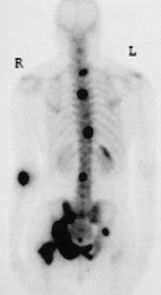

A third diagnostic sensitive in the task of  searching for matastatic cancer is "Skeletal Scintigraphy".

A short-lived radioactive isotope such as technitium is injected into the blood, and after an hour

or so the gamma rays emitted by the isotope are captured by large counters which are able to infer the

postion in the body where the technitium lodged. If there is some metastatic cancer lodged in say the

bones this shows up as a dark region. My scan turned out to be benign with "no evidence of any

bony metastatic desease."